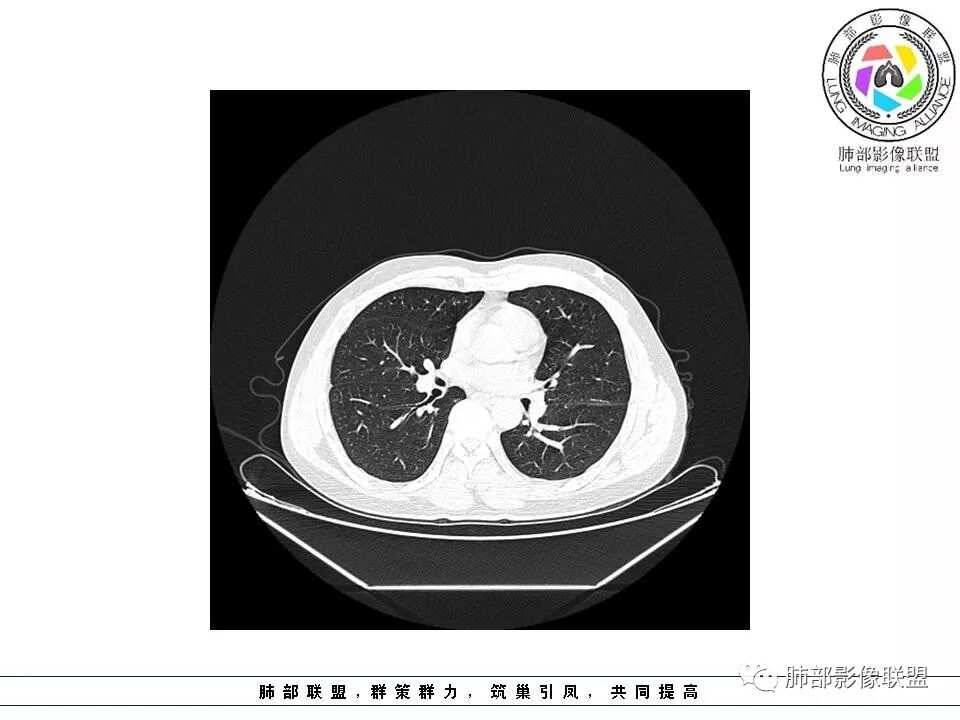

南边:51岁男性,体检发现右肺结节这个年龄段的男性,啥都可以发生,也属于肺癌的高危人群南边:首先是实性还是GGO?好像实性吧

如果实性病变,边缘收缩,可以考虑炎性, 但是边缘有边界清楚GGO,一定要警惕恶性,还有粗短毛刺更要小心撇开其它,看到这个图,除非你怀疑假象,不然就是要考虑腺癌的可能

边界清楚GGO,短毛刺,这要小心瘢痕癌可以多为腺癌复查没变化,与血供有关,属于休眠期张国祯教授的理论:腺瘤样增生、原位癌都属于偏良性,就是没有侵袭性;以后发展——侵袭可以,不变可以,部分可能还会凋亡(比较少)